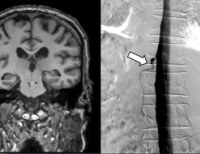

- 남효석 세브란스병원 신경과 교수, 뇌경색 진료 지침 개정 이끌어

- 남효석 연세대 세브란스병원 신경과 교수가 최근 발표된 미국심장학회, 대한뇌졸중학회의 급성 뇌경색 진료 지침 개정을 이끌어냈다. 급성 뇌경색은 혈전이 ...